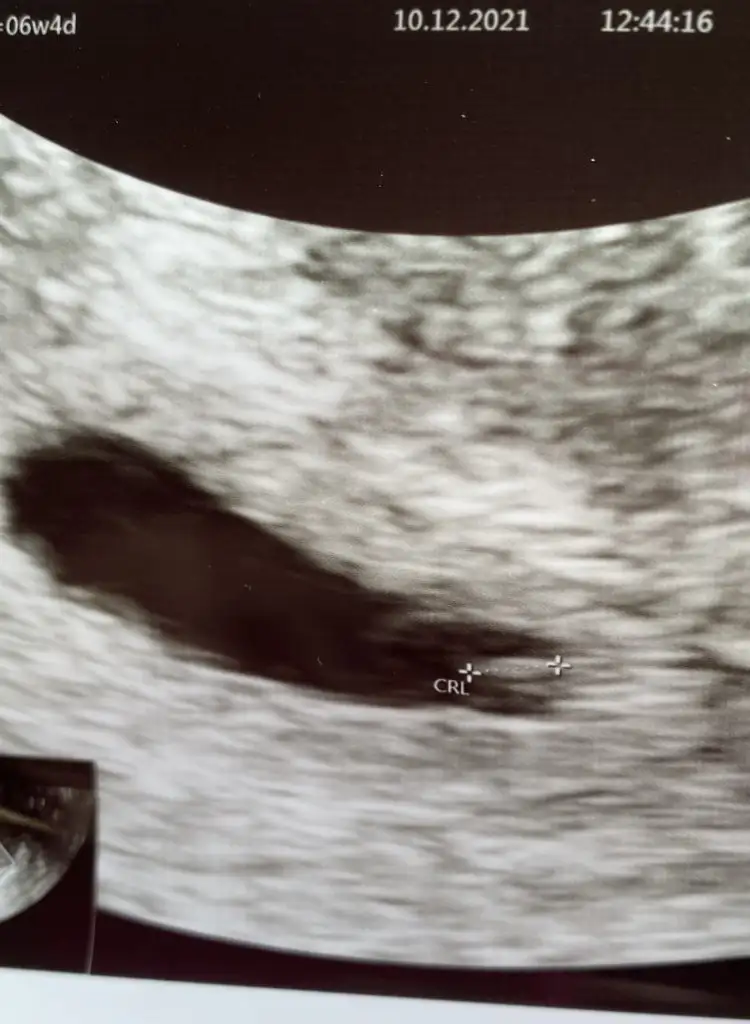

Ayy hayirli olsun darisi kucagina almaya. Darisi bizlereDoktordan çıktım şimdi geçen gittiğimde alttan görebilmişti şimdi karından göründü rahat kalbi de duyduk şükür normalde 6+2 im bugün 6+0 çıktı iki gün ileri atalım satı dedi 29-30 ekimden hesaplayacaz artk

Ben erkek diorum kese seklinden dolayiBen de bugün kontrole gittim 6+4 teyiz 3 mm olmuşuz kalbimiz de atıyor çok şükürÜstümden büyük bir yük kalktı Foti de koyiyim bu haftada cinsiyet tahmini yapılıyomuş belki fikri olan olur

Erkek benceBen de bugün kontrole gittim 6+4 teyiz 3 mm olmuşuz kalbimiz de atıyor çok şükürÜstümden büyük bir yük kalktı Foti de koyiyim bu haftada cinsiyet tahmini yapılıyomuş belki fikri olan olur